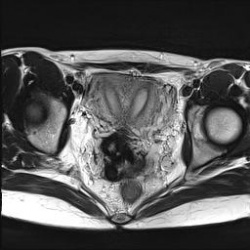

Попалось интересное наблюдение.Обнаружены эндометриома, фиброма и киста. Интересно, что где?